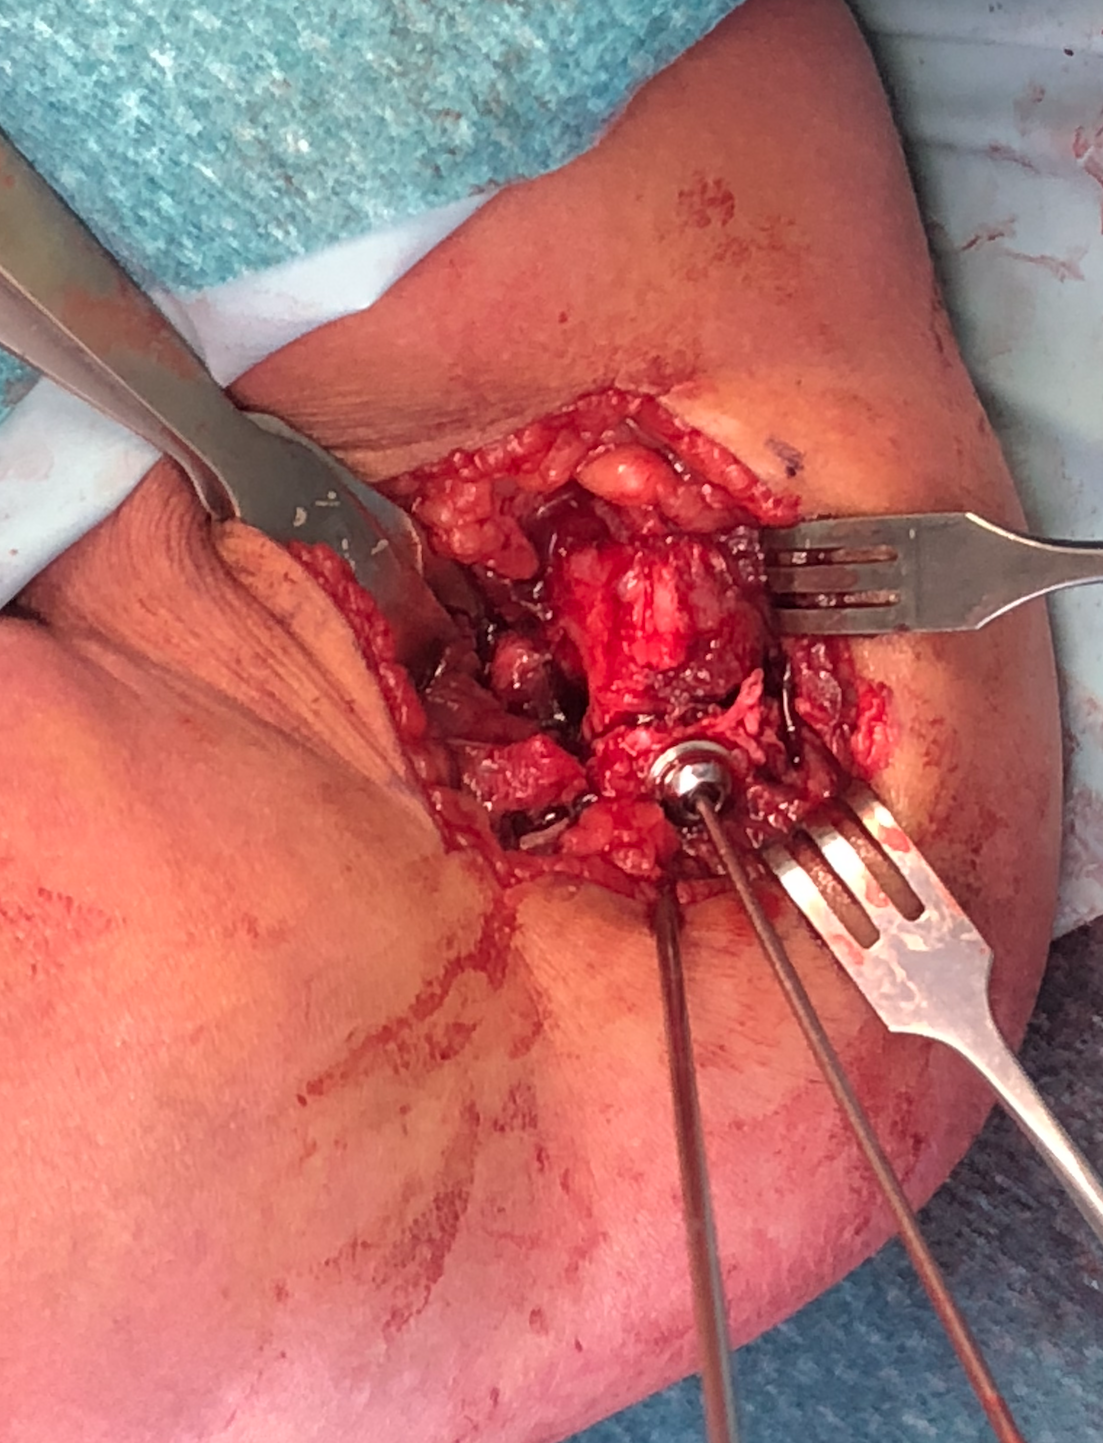

Lateral approach to distal humerus

- curved incision over lateral supracondylar ridge of humerus, and over proximal radius

- proximally intermuscular interval between brachioradialis & triceps

- proximally elevate brachioradialis and ECRL off the distal humerus

- distally split common extensor origin between ECRB and EDC and elevate anteriorly

Don't dissect posteriorly to protect blood supply

Don't need to dissect distal fragment

Use anterior homan retractor across distal humerus to elevate anterior capsule

- visualize distal joint line and perform anatomical reduction under vision

- one K wire parallel to joint surface across fracture into trochlea

- one K wire at 45 degrees to first engaging medial metaphysis

- bury K wires as need to be in for 6 weeks

Open reduction of displaced lateral condyle in left elbow